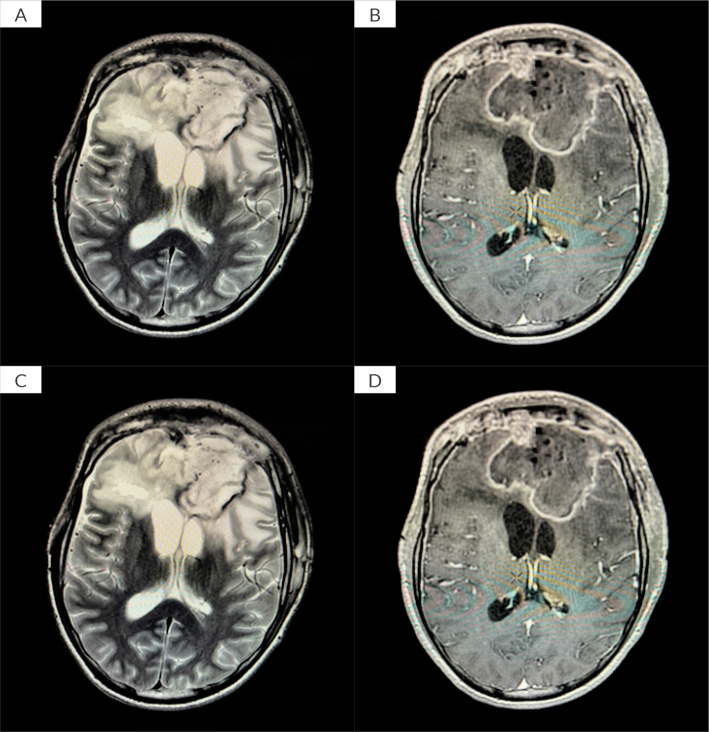

Case description: We present two cases of brain abscess treated at a tertiary care centre using continuous abscess cavity irrigation after conventional interventions proved insufficient. The first patient, a 15-year-old male, experienced recurrent MDR brain abscesses despite multiple surgical procedures and broad-spectrum antibiotics. Initiation of continuous irrigation, combined with targeted antimicrobial therapy, resulted in rapid clinical stabilisation and marked radiological improvement, with minimal long-term sequelae. The second patient, a 65-year-old female, developed multiple brain abscesses after traumatic brain injury and decompressive surgery. Although continuous irrigation effectively controlled the intracranial infection and imaging confirmed resolution, her neurological recovery was limited due to profound pre-existing brain damage.